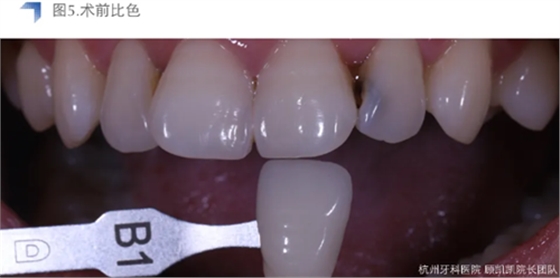

待贴面制作修整完成后,用DMG Vitique Tr.色配套试色糊剂口内试色。

小结:Vitique Tr.在本病例中试色与术后粘接未见明显差异,能恰当表现e.max B1 mt的通透度和明度,美学效果优异。考虑到患牙较近髓,长期随访和术后常规勿咬硬物及冷热刺激,十分必要。